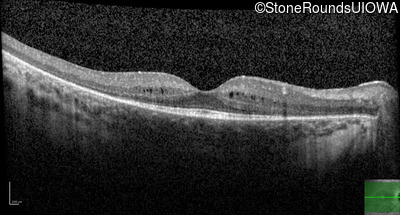

Age at visit: 9 years